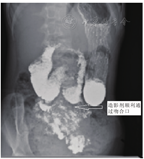

本组4例患儿均在腹腔镜下完成十二指肠空肠吻合术,无中转开腹病例,术中无明显并发症发生,出血少,手术时间120~180 min,平均150 min,无死亡病例。术后第三天至第四天饮水,后转为流质饮食。术后无吻合口漏及吻合口狭窄,无粘连性肠梗阻发生。患儿术后恢复良好,术后腹痛及呕吐等临床症状缓解,术后两周复查消化道造影,造影剂通过顺利,十二指肠梗阻现象消失(图2)。患儿术后1个月体重明显增加了5.25 kg,营养状况得到改善,身体质量指数增大至17.6 kg/m2,P<0.05,差异具有统计学意义。